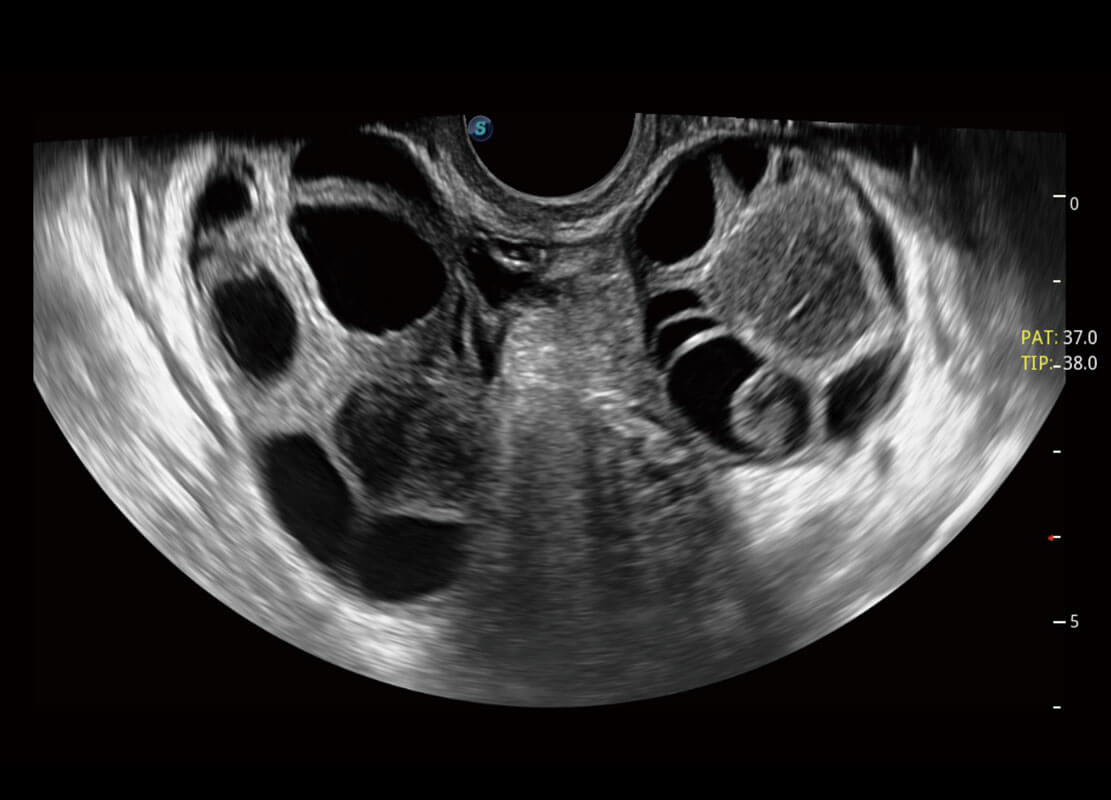

• 腔内妇科-卵巢

P60优异的图像质量搭载专科探头,在妇科基础疾病的诊断、卵泡生长的监测、输卵管通畅情况的判别等方面为您提供生殖应用方案。